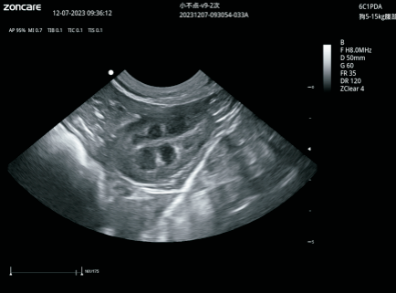

VU60搭载了全新的焕影成像技术平台,采用uSeed全新的CPU+GPU+FPGA硬件架构,多核并行处理技术,搭载高性能单晶体探头和复合晶体探头,可提供更宽带宽、更好穿透力和分辨率的超声影像,精准高效,全面提升临床诊断信心。

卓越的图像质量